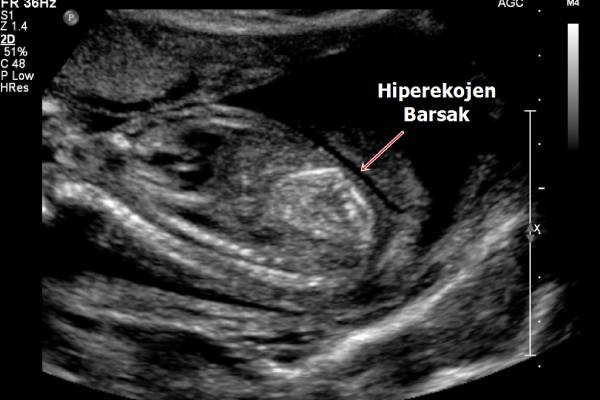

Hiperekojen bağırsak, ultasonografi sırasında bebeğin bağırsağında beyaz, parlak lekeler görülmesidir. Her 100 gebeden 1’inde karşılaşılan bu durum, genellikle hamileliğin ikinci trimesterı denilen 4. – 6. ay arası yapılan kontrollerde saptanır. Bebekte tek başına bağırsak parlaklığı olması genellikle endişe edilecek bir durum olmaz. Çoğu zaman hamileliğin ilerleyen aylarında kendiliğinden ortadan kaybolur. Ancak bağırsak parlaklığı saptandıktan sonra eşlik eden başka belirteçlerin olup olmadığı mutlaka incelenmelidir. Çünkü bu tip fetüslerin %60-80’inde bir sağlık problemi olmasa da ufak bir kısmında eşlik eden başka hastalıklar da olabilmektedir.

Anne karnındaki bebeğin bağırsağında parlaklık olması (hiperekojen bağırsak), detaylı ultrason muayenelerinde karşılaşılan bir olgudur. Neredeyse 100 gebeden 1’inde görülen bu durum, birçok annenin endişelenmesine sebep olsa da %80’inde herhangi bir problemle karşılaşılmaz ve doğum sağlıklı bir şekilde gerçekleşir. Ancak bazı bebeklerde bağırsak parlaklığı ile birlikte çeşitli hastalıklar bir arada görülebilmektedir. Bu nedenle anne karnındaki bebeğin bağırsağında beyaz nokta görülmesi durumunda mutlaka detaylı tetkikler yapılır ve beyaz lekeye eşlik eden başka belirteçlerin olup olmadığı kontrol edilir.